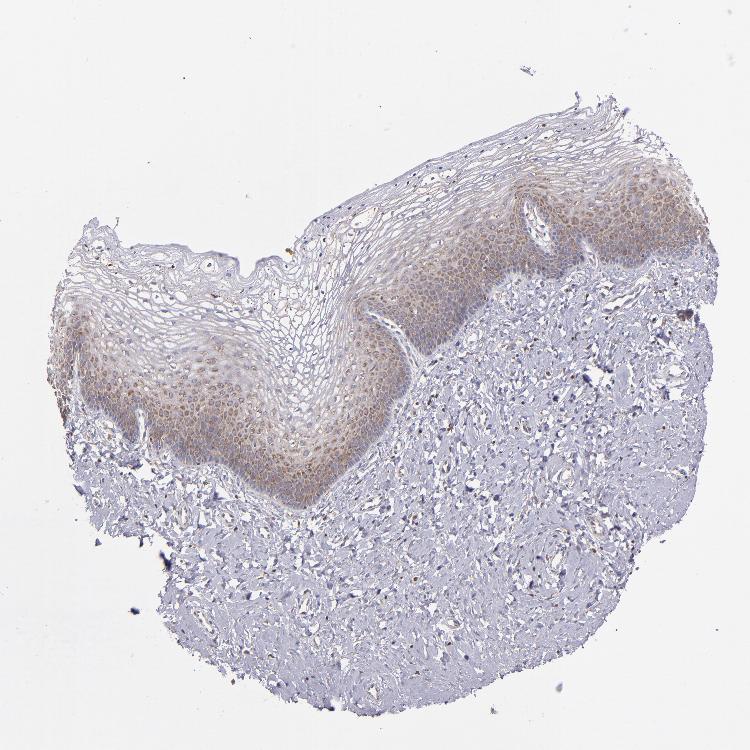

VAGINA - Antibody stainingi

Antibody staining in the annotated cell types in the current human tissue is reported as not detected, low, medium, or high, based on conventional immunohistochemistry profiling in selected tissues. This score is based on the combination of the staining intensity and fraction of stained cells.

Each image is clickable and will lead to virtual microscopy that enables deeper exploration of all samples and also displays staining intensity scores, fraction scores and subcellular localization as well as patient and tissue information for each sample.

Antibody HPA001619Antibody HPA002078

Squamous epithelial cells MediumHigh